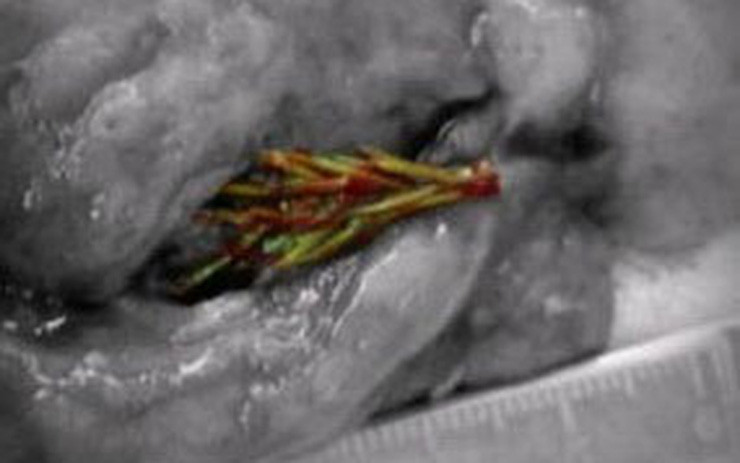

| Cây linh sam có kích thước khoảng 5cm nằm gọn trong lá phổi của anh Artyom. |